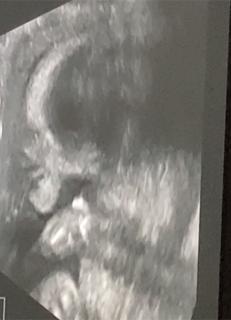

下を向いていますが、目鼻立ちがハッキリしていてパパ似だってわかって嬉しかったです